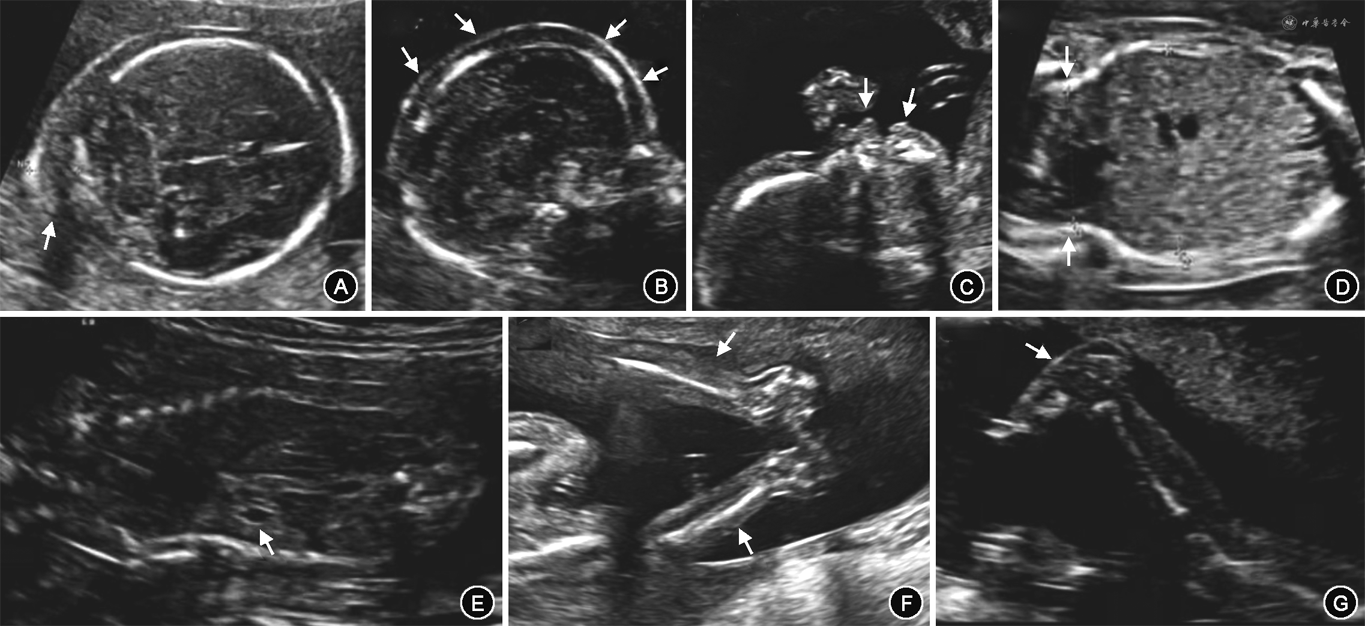

孕妇26岁,孕2产0。因孕21周外院产前超声检查提示“胎儿水肿可能”于2020年9月17日转入福建医科大学附属第一医院。此次妊娠孕妇从未感到胎动。孕21周+4复查产前超声显示胎儿头部皮下组织增厚、颈后皱褶厚度(nuchal fold,NF)增厚;口部呈微张状态,检查时始终未见明显吞咽动作;胸廓狭小、胃泡明显缩小;四肢姿势异常、固定:上肢呈半屈曲状态,下肢呈伸直状态,反复检查始终未见肢体运动,双足后跟软组织回声增厚,呈摇椅足畸形,形似“蜡像娃娃”(图1);羊水处于正常范围(最深径5.37 cm)。超声印象:胎儿运动不能畸形序列征(fetal akinesia deformation sequence,FADS)可能。该孕妇第1次妊娠因“胎儿畸形”于孕25周引产一女婴,该女婴产前染色体核型分析正常,染色体微阵列分析未检出染色体非整倍体或100 kb以上已知的、明确致病的基因拷贝数变异。夫妇双方均未行染色体检查,平素均体健,否认近亲婚配,否认家族及遗传病史。

经超声科及妇产科多学科会诊后,考虑FADS可能性大,预后极差。该夫妇考虑此次妊娠胎儿超声征象与前次妊娠相仿,遂决定终止妊娠。于孕22周+1引产一死男婴,其外观多发畸形:头部及颈部水肿增厚、松弛;呈张口状态,四肢关节僵硬、姿势固定:双肘关节呈屈曲状,双踝关节稍屈曲,双髋关节、膝关节呈伸直状态,双足呈摇椅足畸形(图2)。与产前超声检查结果相符。取引产胎儿腓肠肌组织和父母外周血行全外显子组测序(广州嘉检医学检测有限公司),检测到RAPSN基因(在线人类孟德尔遗传数据库编号*601592)复合杂合变异:c.149_153delinsAGATGGGCCGCTACAAGGAGATGG(p.V50Efs*114)和c.227T>C(p.L76P)。行Sanger测序验证,结果显示这2个变异分别遗传自父亲及母亲(均为杂合子),见图3和图4。根据美国医学遗传学与基因组学学会的变异解释标准和指南[1],父源变异(p.V50Efs*114)为致病性变异(证据等级为非常强1+中等2+支持证据5+支持证据3),美国生物技术信息中心数据库收录编码为rs1131691986;母源变异(p.L76P)为临床意义未明变异(证据等级为中等2+支持证据3),美国生物技术信息中心数据库未有该变异记录。在线人类孟德尔遗传数据库中收录RAPSN基因与FADS 2型(孟德尔遗传病表型编号#618388)有关,遗传方式为常染色体隐性遗传。根据胎儿的临床诊断结果推测,母源变异(p.L76P)为本例胎儿新发致病性变异,故引起胎儿表型的遗传学原因为RAPSN基因上2个致病性变异的复合杂合变异,胎儿确诊为FADS。